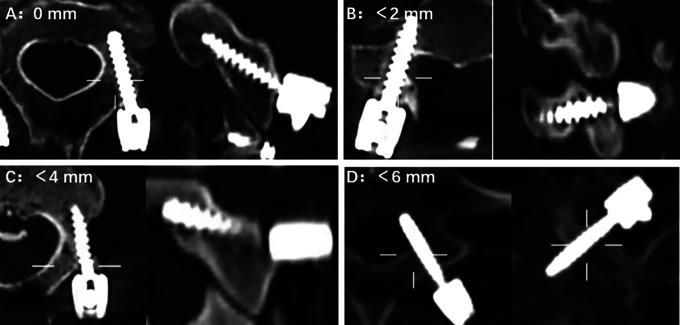

This study included 58 patients. The primary outcome measures were the 1-time success rate and the accuracy of pedicle screw placement according to the Gertzbein-Robbins scales. The secondary outcome measures, including the operative time, intraoperative blood loss, hospital stay, cumulative radiation time, radiation dose, intraoperative advent events, and postoperative complications, were recorded and analyzed. The Japanese Orthopedics Association (JOA) scores and Neck Disability Index (NDI) were used to assess the neurological function of patients before and at 3 and 6 months after surgery.

The rate of grade A was significantly higher in the RA group than in the FG group (90.6% and 71.1%; < .001). The clinically acceptable accuracy was 97.2% in the RA group and 90.7% in the FG group ( = .009). Moreover, the 1-time success rate was significantly higher in the RA group than in the FG group. The RA group had less radiation time ( < .001) and less radiation dose ( = .002) but longer operative time ( = .001). There were no significant differences in terms of intraoperative blood loss, hospital stay, intraoperative adverse events, postoperative complications, JOA scores, and NDI scores at each follow-up time point between the 2 groups.